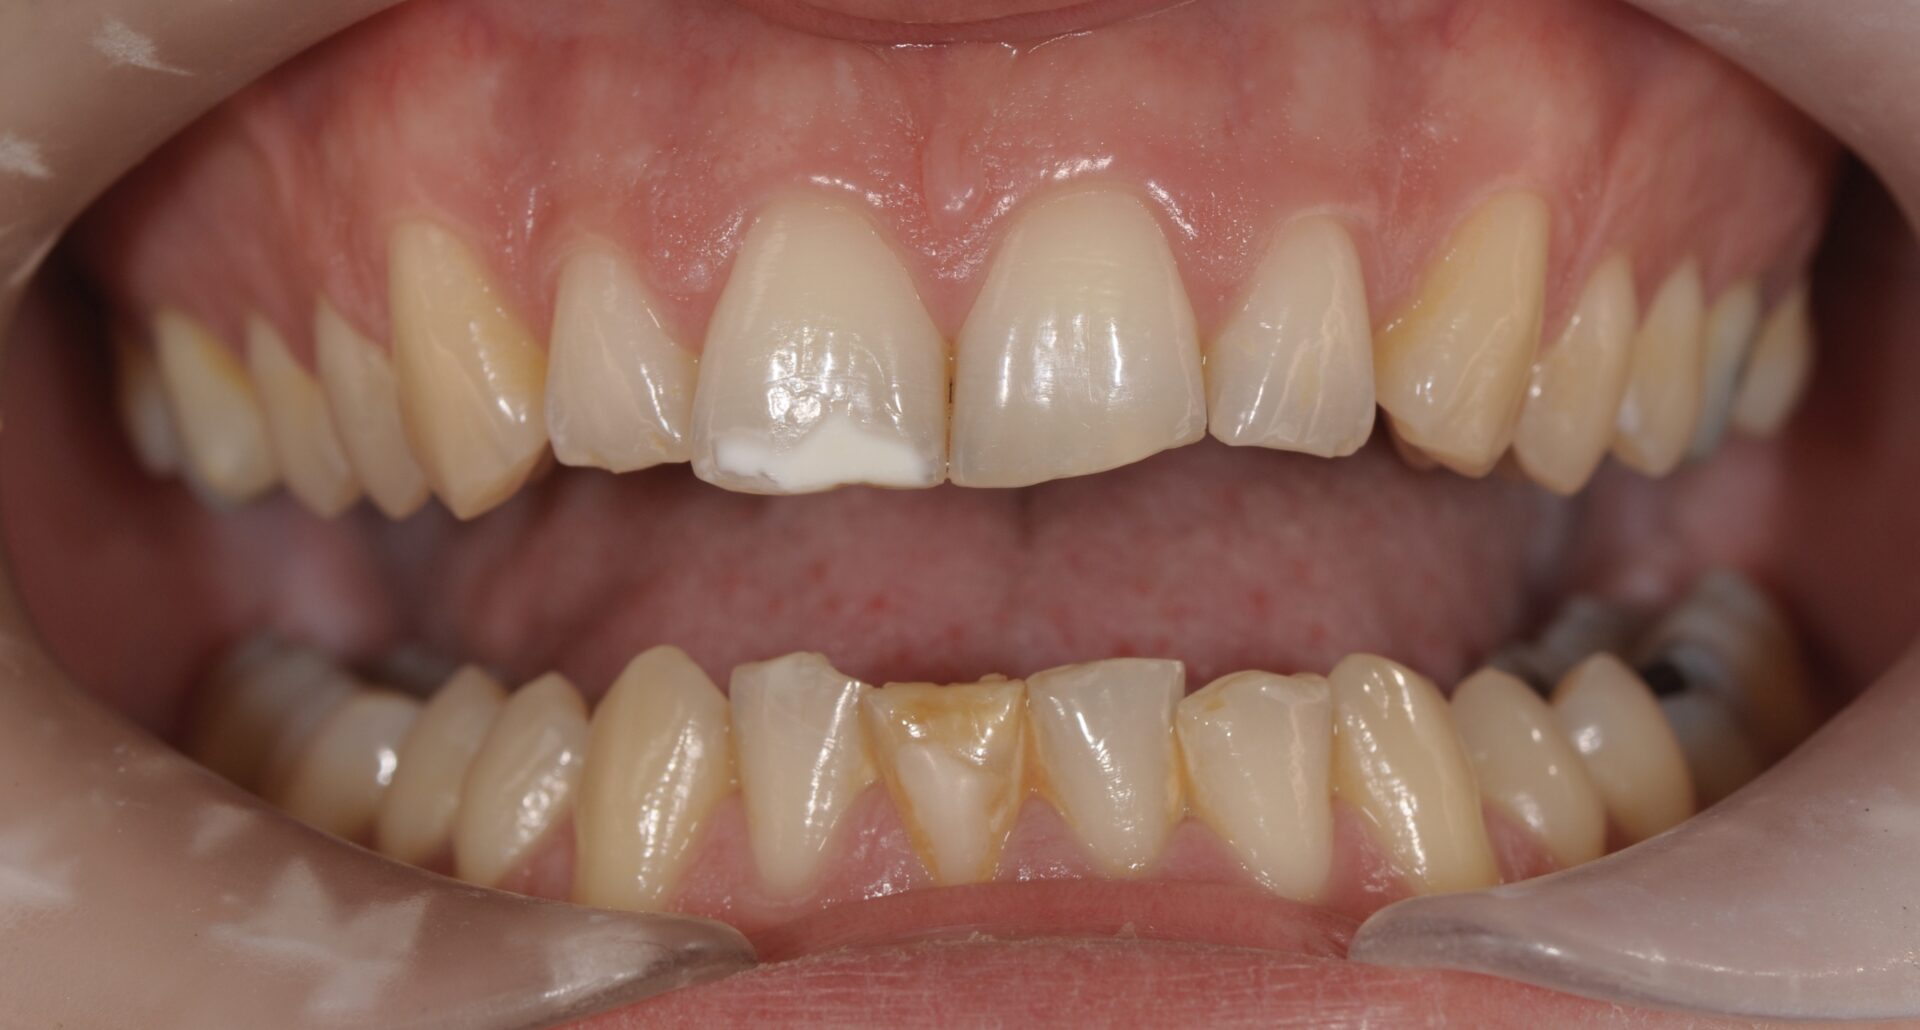

Si en antérieur, le préjudice esthétique n’est pas trop important et qu’il n’y a pas de perte de substance, il est conseillé d’attendre la majorité afin de réaliser un éclaircissement suivi de la technique d’érosion infiltration (ICON), plus ou moins une stratification de composite esthétique (Figures 8-9-10).

formation dentaire pédodontie Figure 8.

formation dentaire pédodontie Figure 9.

formation dentaire pédodontie Figure 10.

Figures 8-9-10 : Traitement antérieur, éclaicissemet bouche complète, ICON et stratification de

composite sur 11 (l’éclaircissement ayant suffit pour la 41)